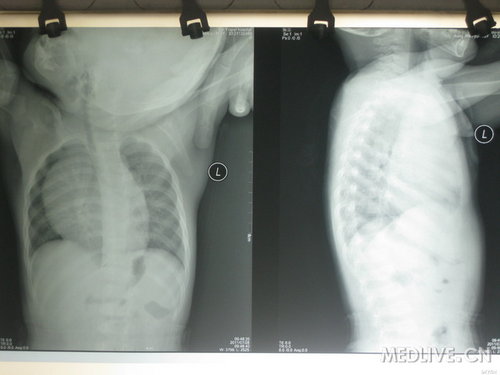

患儿,男性,2岁4个月,回族。家长代诉“发现颈部包块伴气短2个月”。

2个月前偶然发现患儿双侧颌下肿起,可触及包块,并出现活动时气短,逐渐加重,跑动时呼吸急促,严重时可跌坐在地喘息约数分钟后缓解。近1周来出现鼻塞、流清涕,偶有咳嗽,在当地诊所予“抗感冒”治疗(具体不详)无好转,颈部两侧包块增大,平卧位时喘息加重。无发热、盗汗,无水肿,饮食稍减少,睡眠不安,二便正常。

查体:T36.7?C,R36次/分,P122次/分。发育正常,营养良好。双侧颌下及耳后、颈部可触及多个肿大淋巴结,基本对称分布,质中,无压痛,活动度差,无粘连。心率122次/分,心浊音界向右上扩大。余(-)。

胸部正侧位X光片:右肺可见半圆形状边缘清密度增高影(胸腺增大),膈影光整,弧度存在,肋膈角显示锐利。

心脏彩超:心脏大小、结构未见明显异常,右室面上部可见一半圆形类胶冻状密度影,大小约6cm*4cm*4cm.